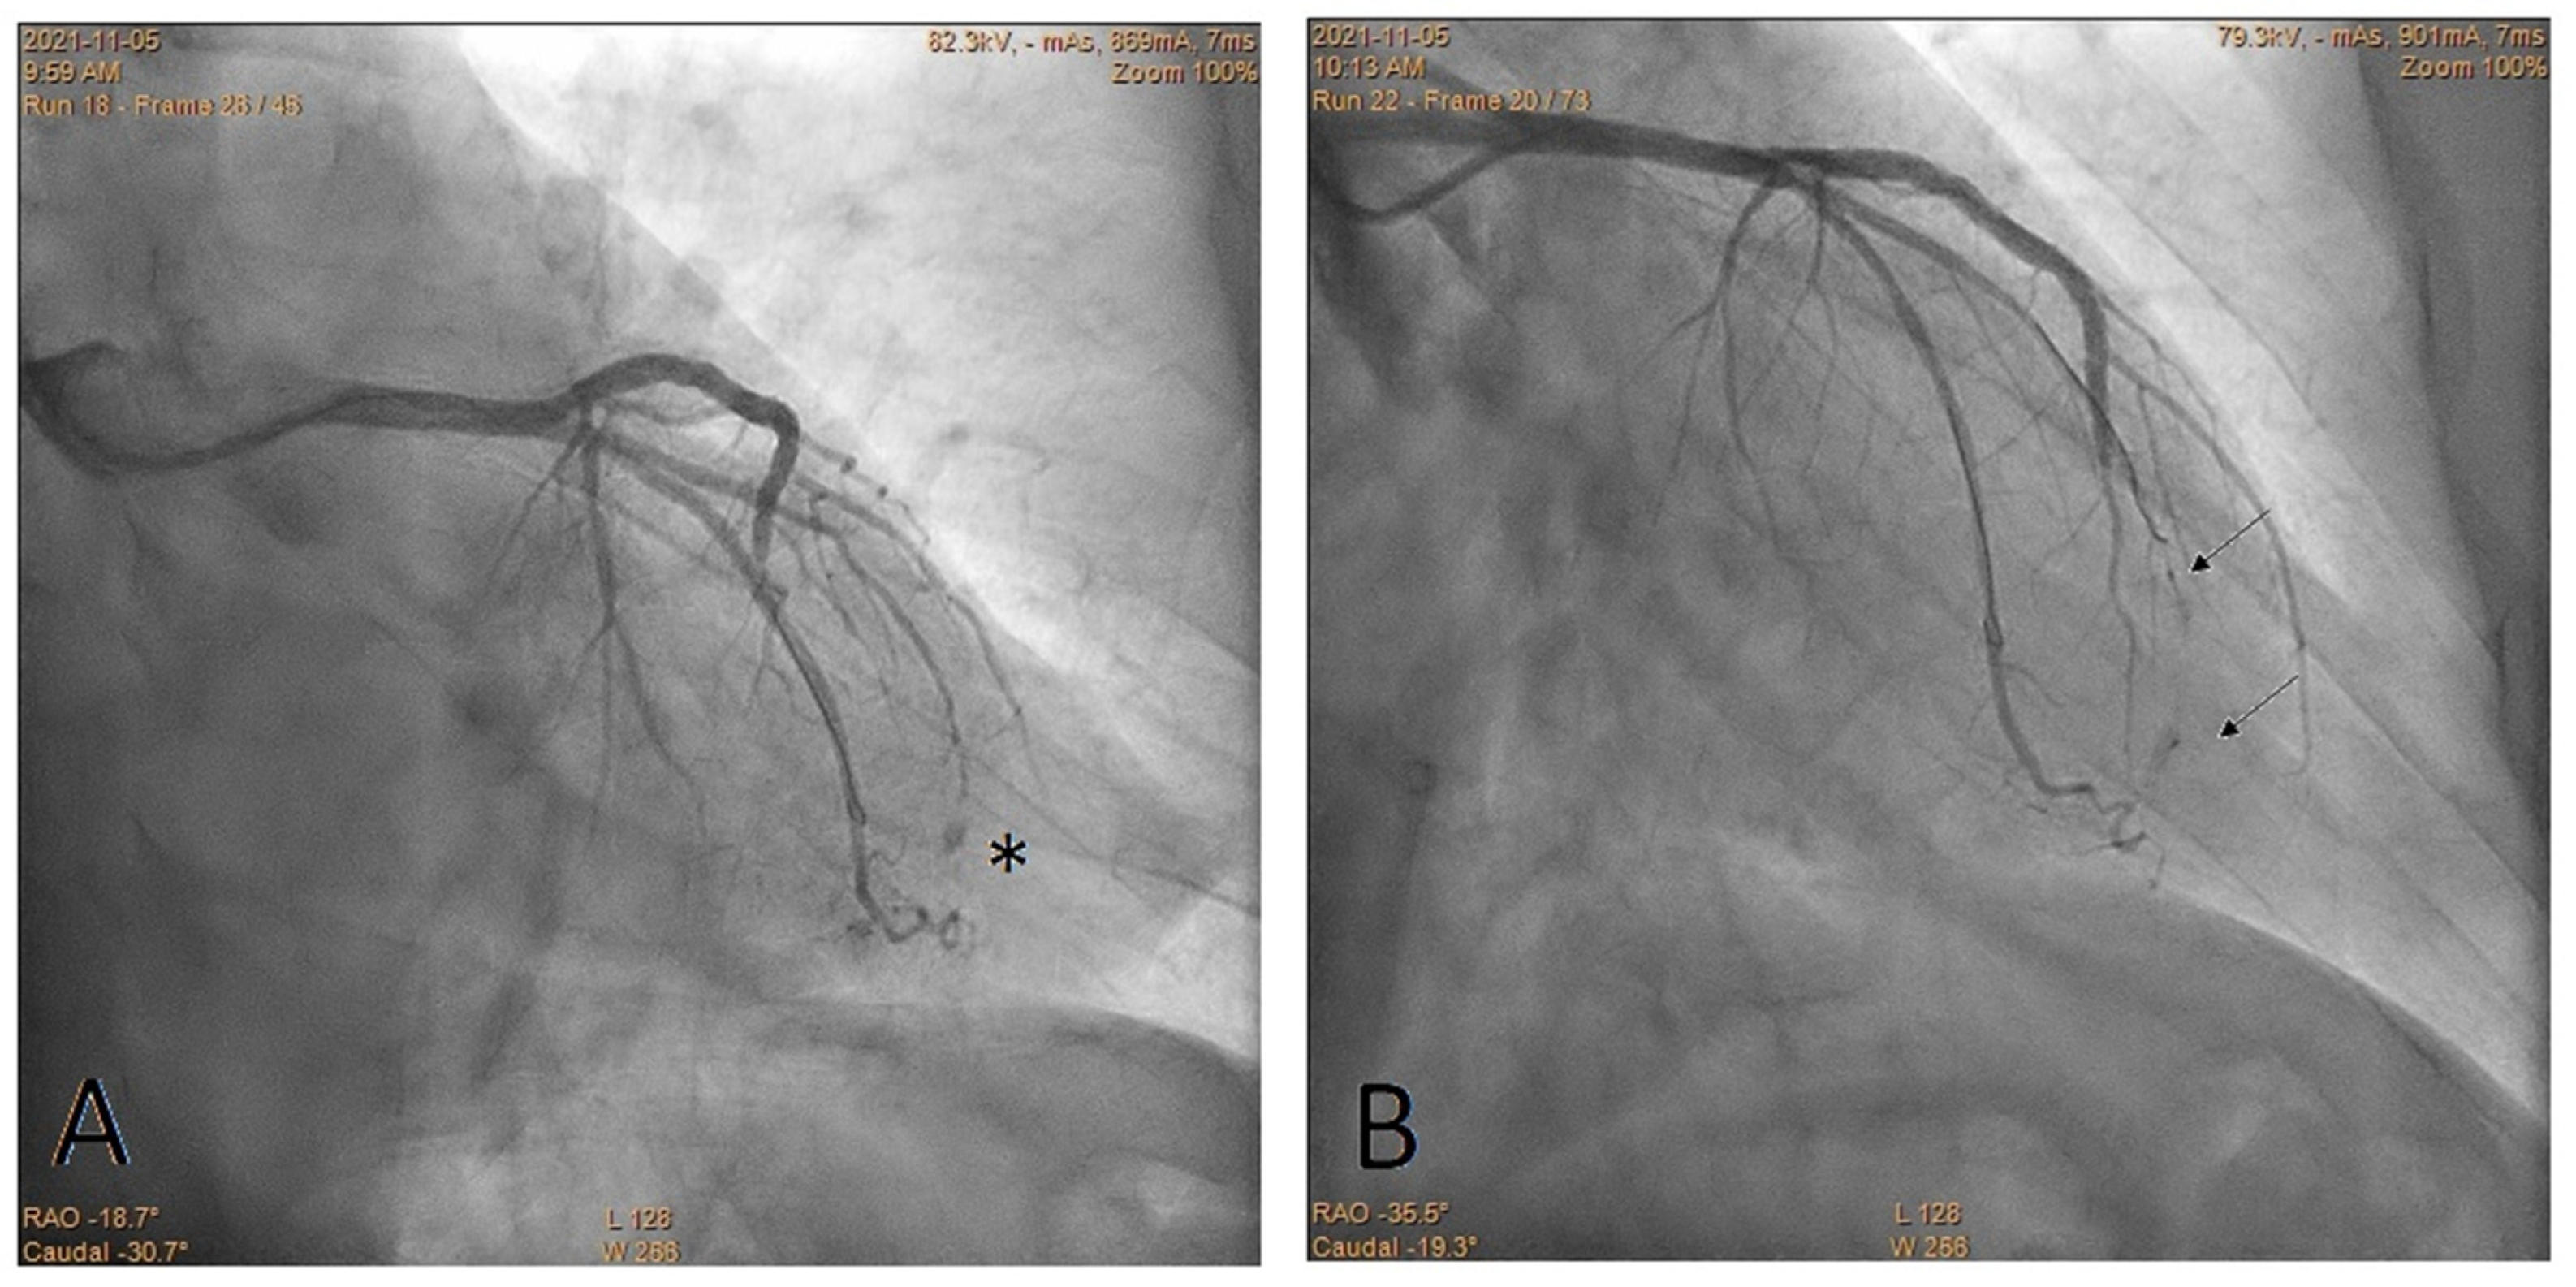

Embolization of Perforated Coronary Artery with a Fragment of Balloon Catheter (Cut Balloon Technique)—Multicenter Study

2. Methods

3. Results